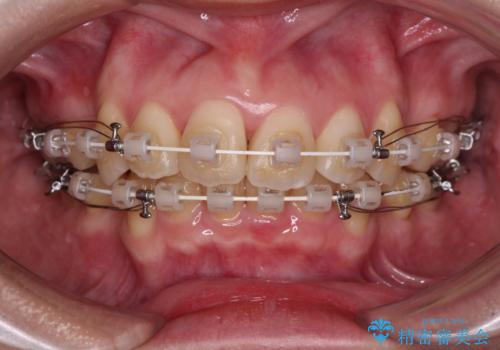

【モニター】横顔のシルエットをスッキリと ワイヤー装置による抜歯矯正治療

- 審美装置

- 前歯のデコボコと突出感を気にして来院された患者様です。

上下左右第一小臼歯4本を抜歯して、積極的に口元を引っ込めるよう、ワイヤー装置にて矯正治療を行うこととしました。